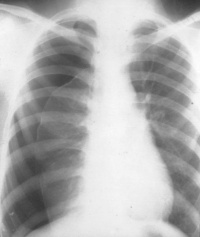

X线胸片检查是诊断气胸的重要方法,可显示肺受压程度,肺内病变情况以及有无胸膜粘连、胸腔积液及纵隔移位等。气胸的典型X线表现为外凸弧形的细线条形阴影,称为气胸线,线外透亮度增高,无肺纹理,线内为压缩的肺组织。大量气胸时,肺脏向肺门回缩,呈圆球形阴影。大量气胸或张力性气胸常显示纵隔及心脏移向健侧。合并纵隔气肿在纵隔旁和心缘旁可见透光带。

肺结核或肺部慢性炎症使胸膜多处粘连,发生气胸时,多呈局限性包裹,有时气胸互相通连。气胸若延及下部胸腔,肋膈角变锐利。合并胸腔积液时,显示气液平面,透视下变动体位可见液面亦随之移动。局限性气胸在后前位胸片易遗漏,侧位胸片可协助诊断,或在x线透视下转动体位可发现气胸。

CT表现为胸膜腔内出现极低密度的气体影,伴有肺组织不同程度的萎缩改变。CT对于小量气胸、局限性气胸以及肺大疱与气胸的鉴别比X线胸片更敏感和准确。

气胸容量的大小可依据x线胸片判断。由于气胸容量近似肺直径立方与单侧胸腔直径立方的比率[(单侧胸腔直径。一肺直径。)/单侧胸腔直径。)],侧胸壁至肺边缘的距离为1cm时,约占单侧胸腔容量的25%左右,2cm时约50%。故从侧胸壁与肺边缘的距离≥2cm为大量气胸,<2cm为小量气胸。如从肺尖气胸线至胸腔顶部估计气胸大小,距离≥3cm为大量气胸,<3cm为小量气胸。

(一)X线胸部检查:为最可靠诊断方法,可判断气胸程度、肺被压缩情况、有无纵隔气肿、胸腔积液等并发症